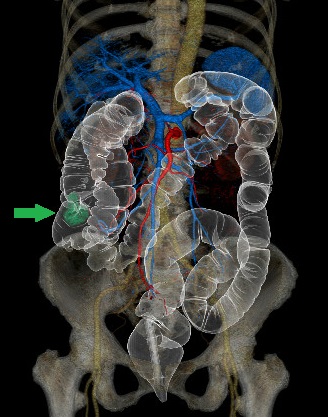

CT検査室

CTコロノグラフィー:上行結腸癌術前検査

当院は大腸CT検査技術施設認定を取得しています